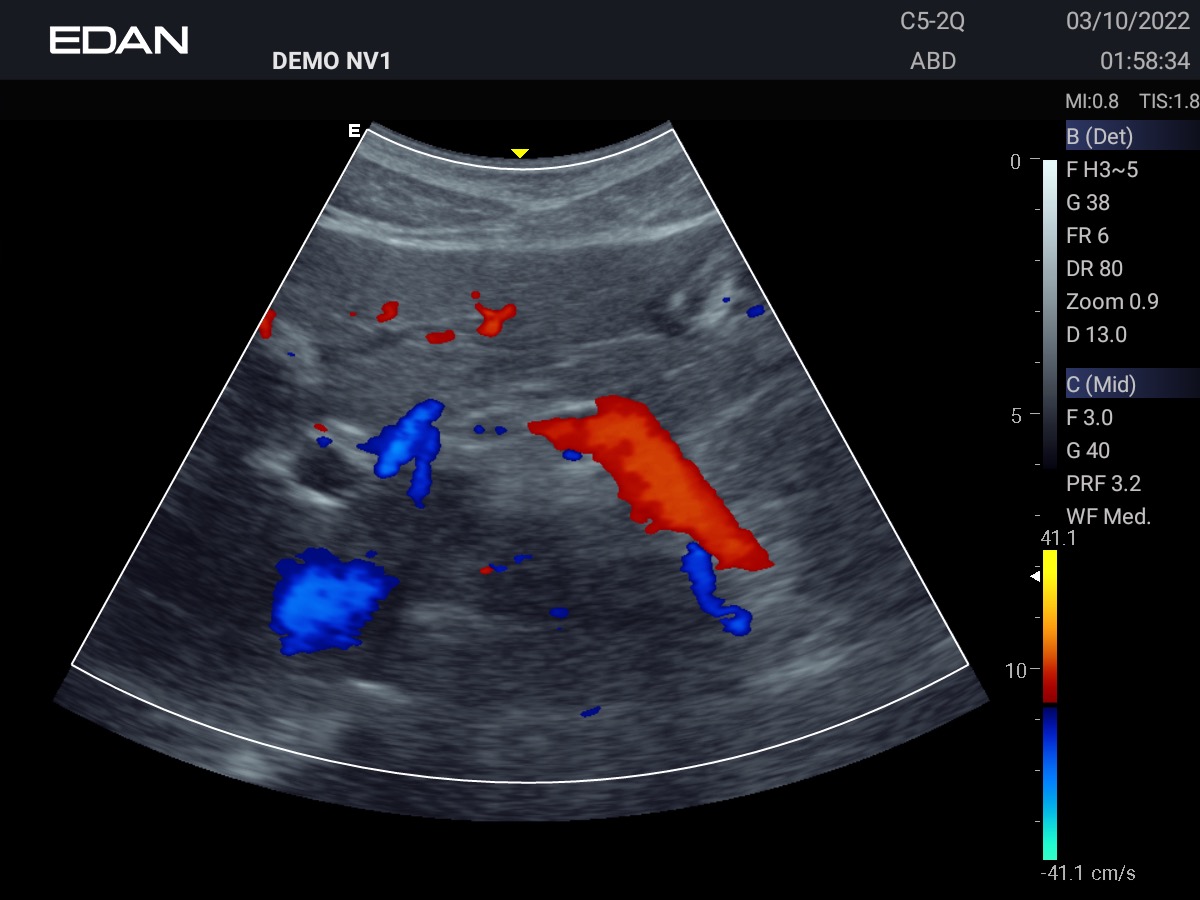

Clareza impressionante

Construído com a inovadora tecnologia Edan TAI e várias tecnologias de processamento de imagem, o Acclarix AX3 pode exibir perfeitamente a imagem de ultrassom em diferentes modos, auxiliando o ultrassonografista a fazer diagnósticos mais precisos.

Galeria de Imagens